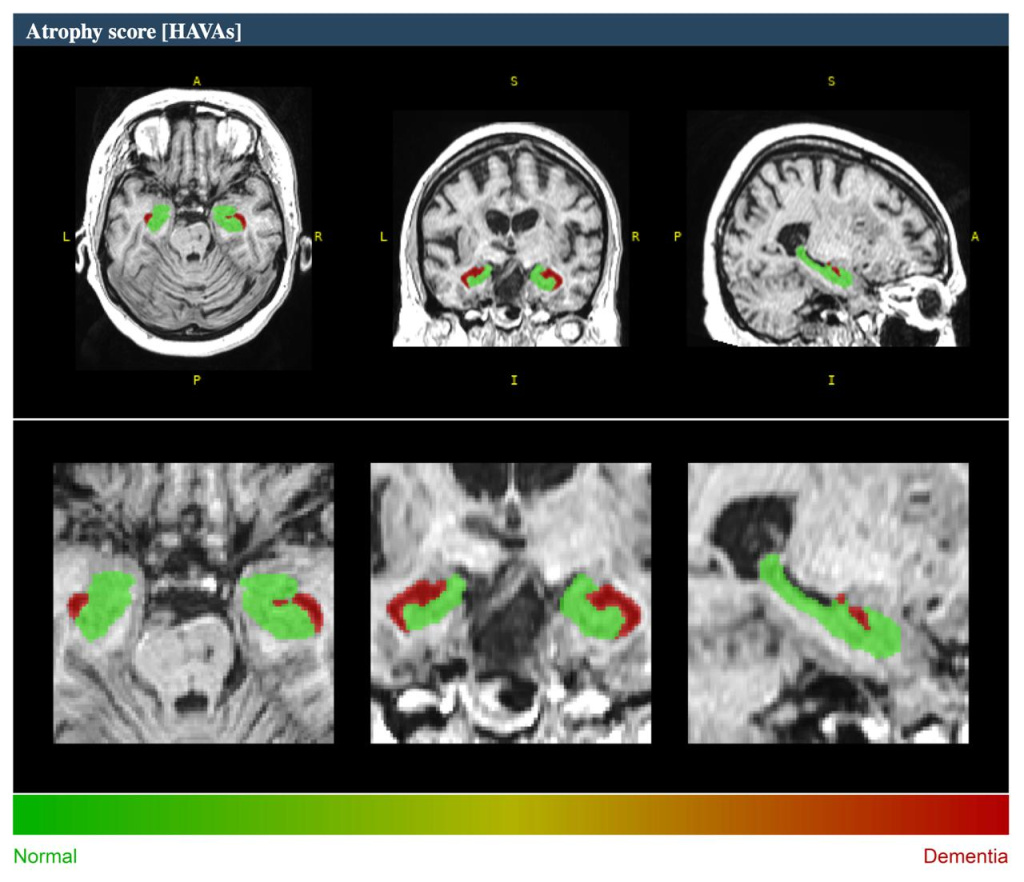

МРТ головного мозга и волюметрия гиппокампов при болезни Альцгеймера

МРТ головного мозга с волюметрией гиппокампов — это современный метод диагностики, который помогает выявить структурные изменения в головном мозге, характерные для болезни Альцгеймера и других нейродегенеративных заболеваний.

Волюметрия гиппокампов — измерение объемов гиппокампов, ключевых структур мозга, отвечающих за память и обучение. Уменьшение их объема часто является ранним маркером болезни Альцгеймера.